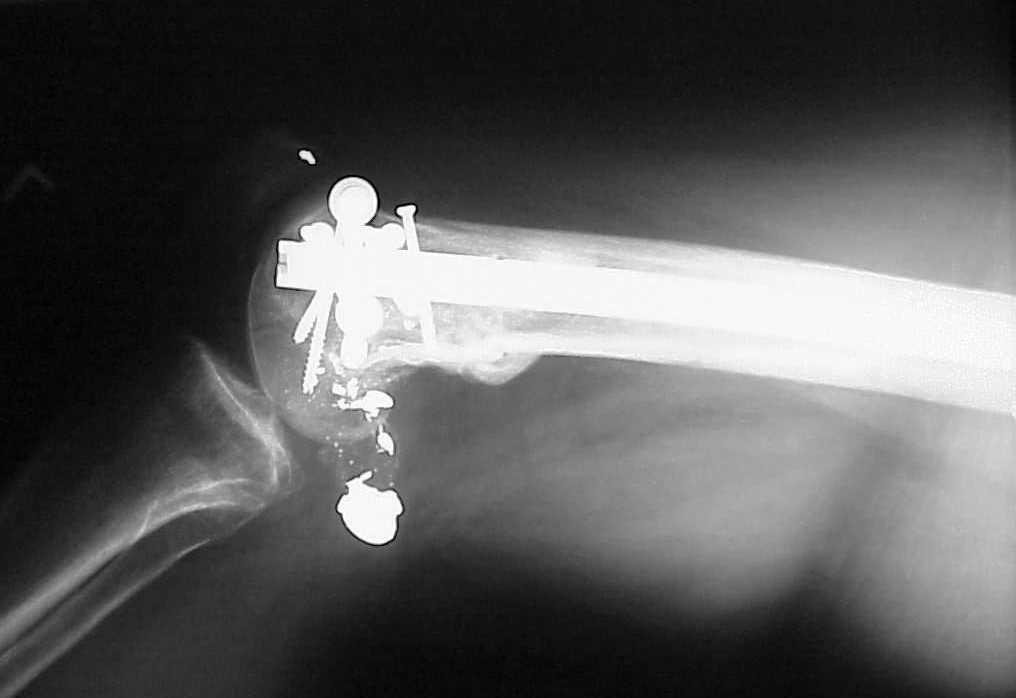

Use 6.5 mm cannulated screws if you have and

place one anterior to where IMN will go if anterior cortex if insufficient and AP screws on either side of the IMN out of the trochlea to provide some additional varus/valgus stability. I worry about the leg going into valgus w/the lack of lateral cortex.

See attached case that was done several years ago before LISS. He had comminuted trochlea and anterior blocking screws were used to prevent anterior IMN cut-out.